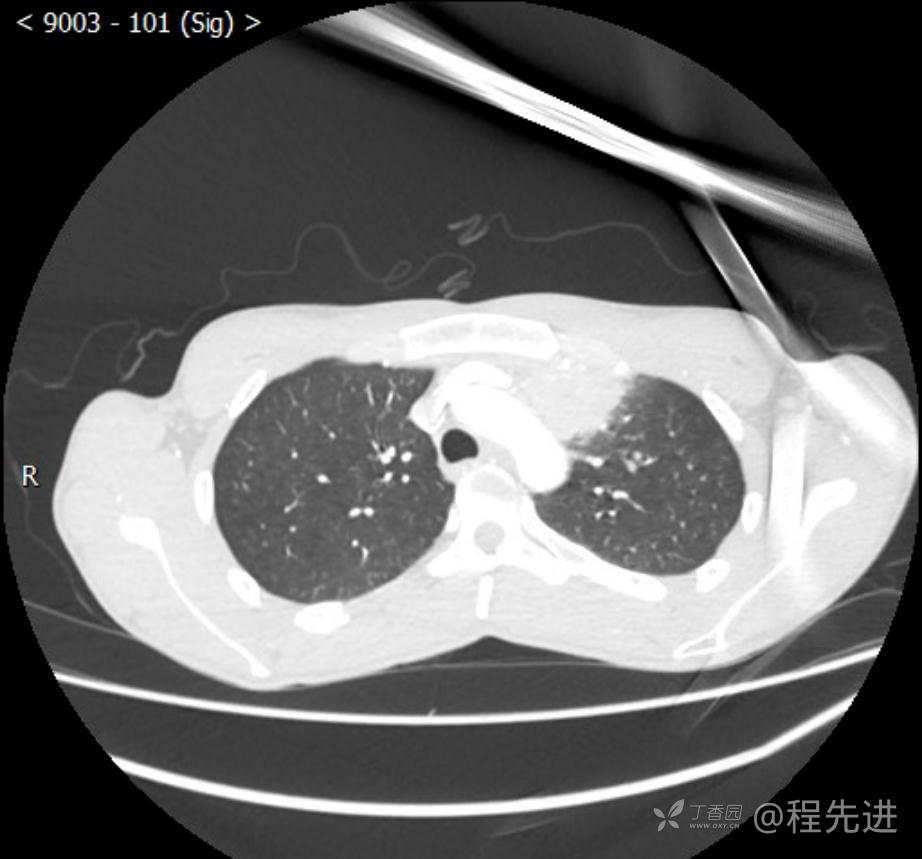

主诉:反复咳嗽1月,发现“纵隔”占位半月,乏力10余天。

现病史:患者1月前无明显诱因出现咳嗽,以夜间为著,伴有少量白痰,无发热,无胸痛、咯血,无痰中带血,未予重视,半月前外院行胸部CT检查发现“左前上纵隔”占位,未予进一步检查及治疗。近10余天自觉乏力,逐渐加重。